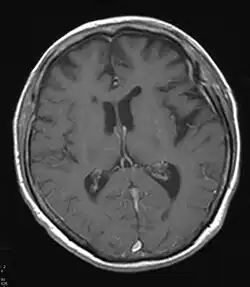

Neben klinischen Verdachtsmustern kann in vivo eine nuklearmedizinische Diagnostik mit Darstellung der Gehirnperfusion (mit 99mTc-HMPAO) (SPECT) oder des Glucose-Stoffwechsels des Gehirns mit 18FDG (PET) weiterhelfen – typischerweise sind in den Gehirnabschnitten, die dem Krankheitsnamen (frontotemporal) entsprechen, die Durchblutung und der Glucose-Stoffwechsel herabgesetzt.